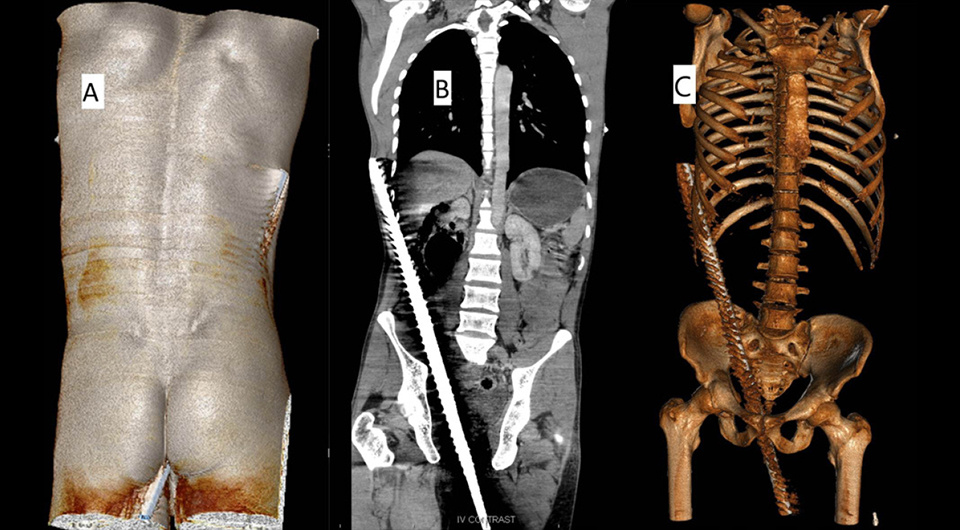

Nandakumar B M et al. / BMJ Case Reports, 2025

На компьютерной томографии визуализировали металлическое инородное тело, вошедшее через перианальную область и седалищно-анальную ямку сзади и сбоку от простаты и мочевого пузыря. Оно прилегало к правым внутренней запирательной и подвздошной мышцам и проходило в забрюшинное пространство спереди и латерально от большой поясничной мышцы. Далее оно шло рядом со слепой и восходящей толстой кишкой в правом латеральном канале брюшной полости, выходя через 10 и 11 межреберный промежутки справа. Также было видно скопление воздуха в забрюшинном пространстве и свободной жидкости в брюшной полости, признаков активного кровотечения не было. Общий анализ крови оказался нормальным.